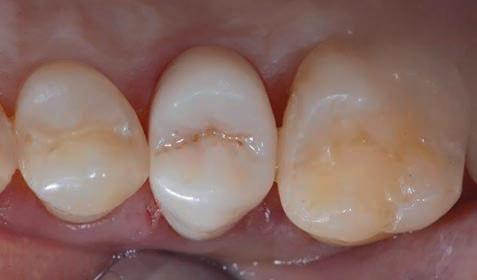

Figure 15, 16 &17: Views of the monolithic restoration in lithium disilicate, polished and finished.

Additionally, the ultra-thin structure of the Initial LiSi Block permits easily polishing of the restoration even after the occlusal adjustments, leaving the area extremely uniform and smooth. This reduces the finishing times, the brightness lasts longer and the occlusal contacts produce less abrasion of the restoration and of the antagonists (Figs. 15-17).

Figure 23: Final occlusal view. Figure 24: Final occlusal view at higher magnification.